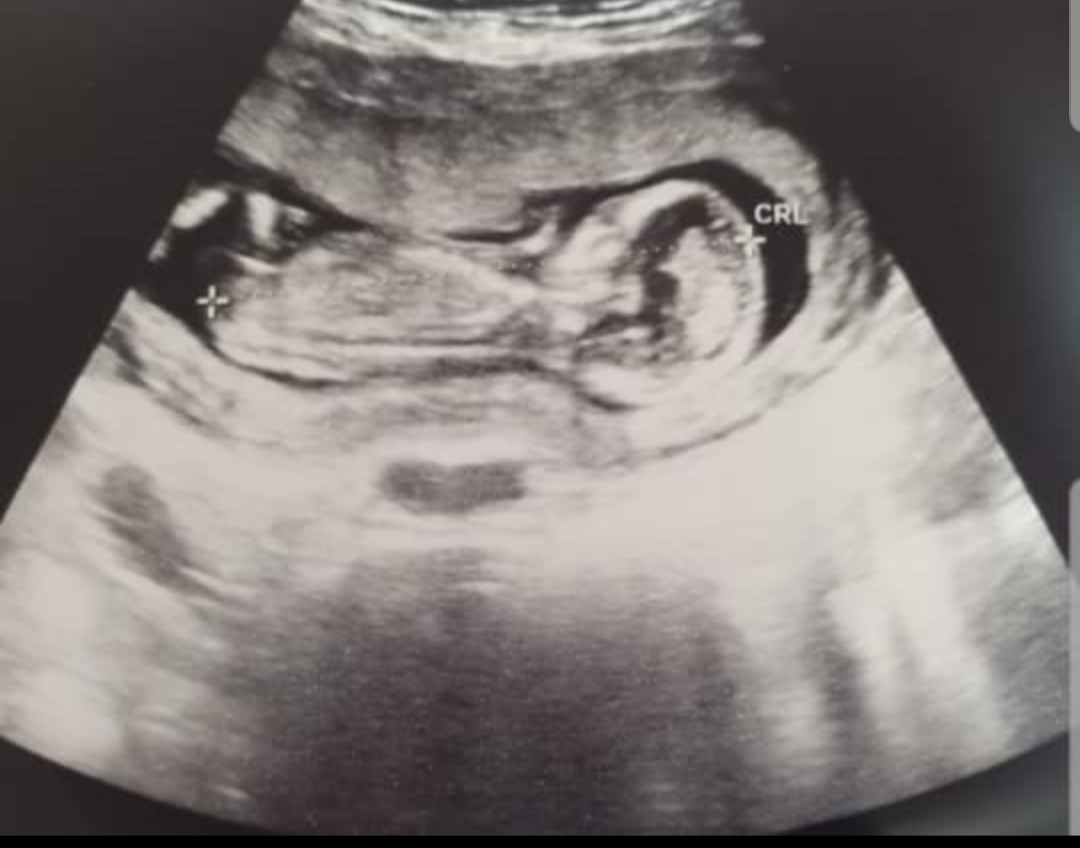

This is a leg and pelvis..is that the gender in the middle?

15 or 16 weeks 4 days.

You couldn't comment on this one either because you said it is hard to tell. Baby is slightly turned. Nub is a bit risen which made me think boy but I have seen 12 week nubs more risen. xx

Sometimes I can piece together two less than optimal pictures to yield an educated guess. Tentative blue lean.

I felt like I might have been seeing a penis and scrotum squashed together in the 20 weeker but was not very sure at all that's what it was, and then the nub seemed possibly angled up so it's a very tentative blue guess. Nowhere near certain but it's just the vibe I get.